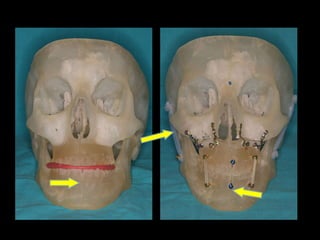

Moldeado previo de la placa

Relación céntrica Sistema de fijación